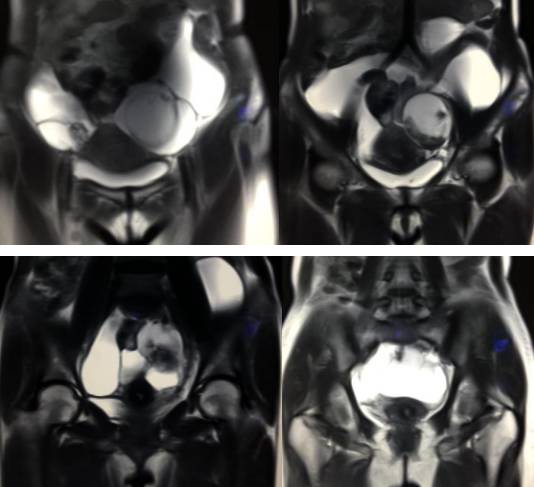

女性,42岁。

主诉:下腹部胀痛不适1月余

病史:自诉13岁时患“结核”,8年前行“左侧附件包块”切除术。

MR检查:

病理结果:黄体血肿

根据时间不同MR信号也有所不同,TIWI脂肪抑制序列可以鉴别脂肪和出血。